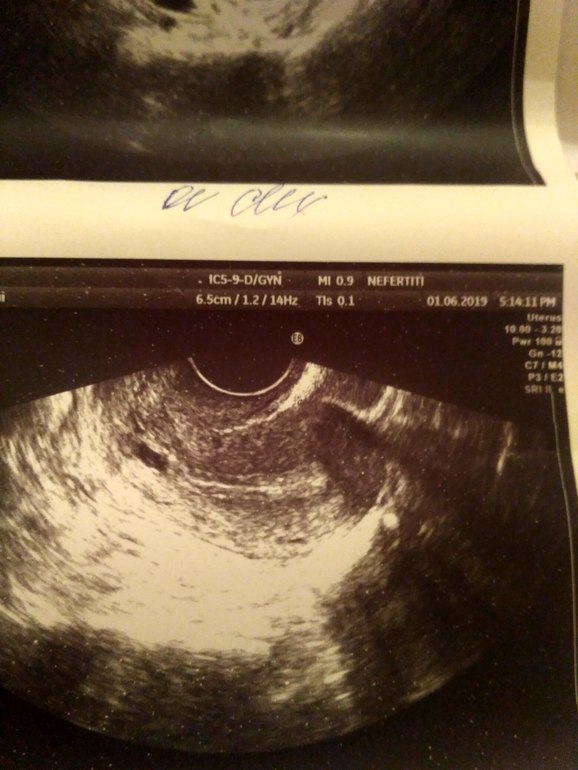

У вас на снимке еще матка. До шейки там далеко. У меня киста вначале ШМ, поэтому мне делают отдельный снимок шейки. Выглядит так. Верхний снимок матка, нижний шейка с кистой.

В матке может быть: беременность, киста, аденомиоз, полип, миома.